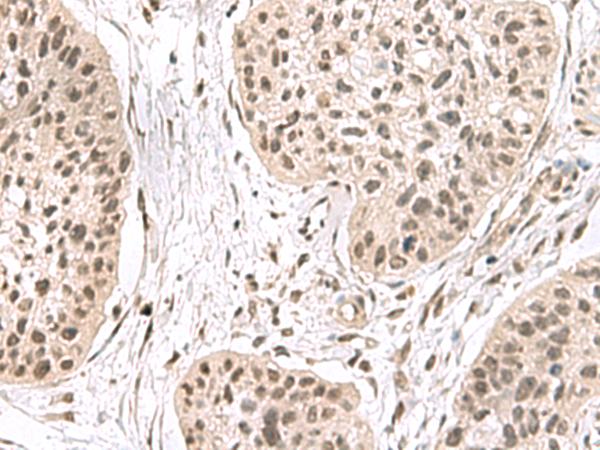

IHC positive control: |

Human esophagus cancer |

40-200 |